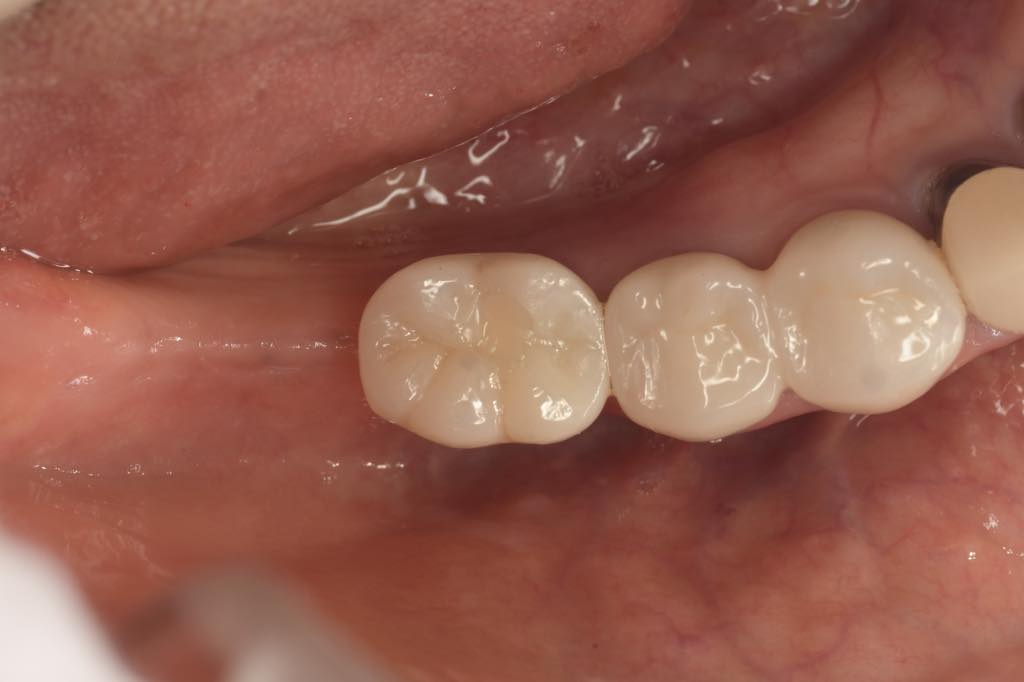

CASE 02

| 主訴 | 右下奥歯が欲しい |

| 治療内容 | 右下6番 インプラント治療 |

| 治療回数 | 8回 |

| 治療費用 | ¥390,000 |

| 想定される副作用 | 腫れ、痛み |